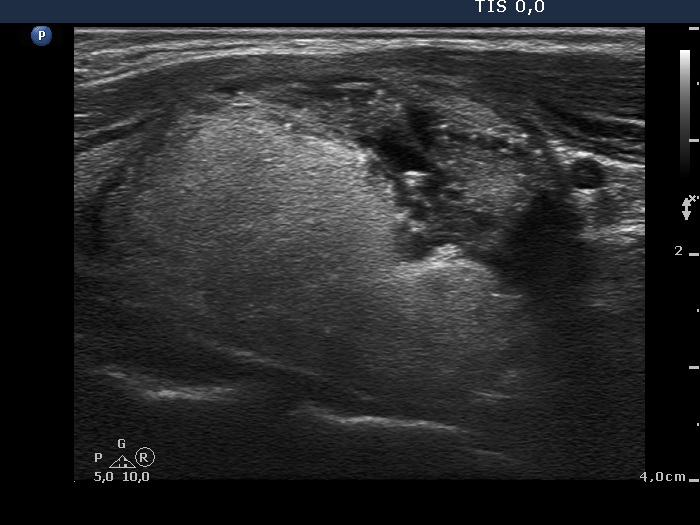

|

Papillary carcinoma (histological diagnosis) - case conp 035 |

The thyroid presented in the left images is composed of moderately hypoechogenic and hypoechogenic nodules, while the lobe in the malignant case is diffusely hypoechogenic and has a less hypoechogenic but more inhomogeneous lesion in its dorsal part. Both the left thyroid and the malignant nodule in the right images have hyperechogenic granules and lines which correspond to a connective tissue.